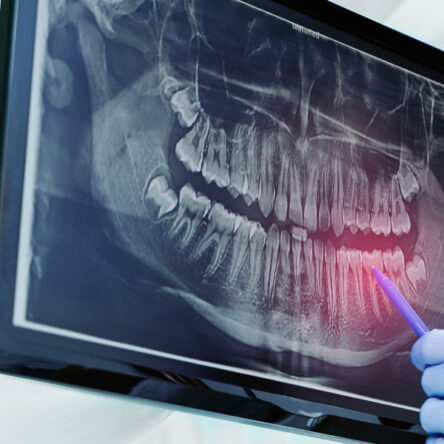

Your journey starts with a complete consultation and 3D digital imaging to assess bone structure and oral health. Patients receiving All-on-4 dental implants benefit from advanced planning, local anaesthesia, and careful implant placement. Our dentist ensures every phase—from surgery to restoration—is completed with precision and your comfort in mind.